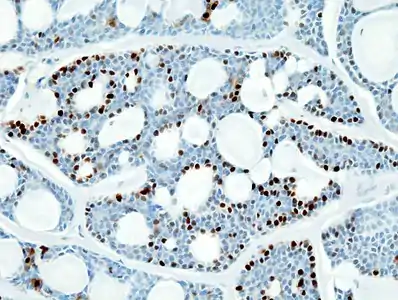

Micrograph of an adenoid cystic carcinoma of a salivary gland (right of image): Normal serous glands, typical of the parotid gland, are also seen (left of image), H&E stain.